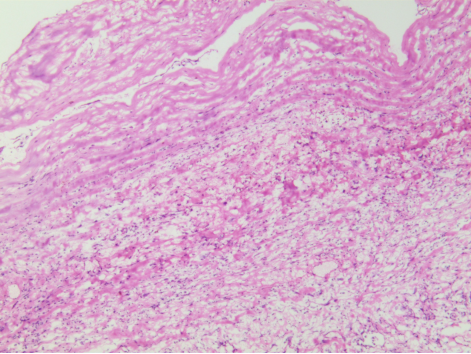

术中冰冻,全称“术中快速冰冻病理诊断”,顾名思义,手术过程中将切取的新鲜组织在低温条件下快速冷却到一定硬度,然后进行切片、染色及诊断的方法,相当于术中的病理科急会诊,那它有多快呢?30分钟内就要给出病理结果,可能这30分钟对患者和术者来说,又何尝不是世界上最漫长的30分钟呢。

术中冰冻虽然及时快速,但有一定的局限性!首先,标本是在低温下快速冷冻切片,未经充分固定和处理,会导致组织过度收缩变形,组织中含有较多水份,制片过程中容易产生冰晶,从而影响观察;其次,因取材有限,可能选取的组织不具有较强的代表性;最后,时间紧迫等因素,导致冰冻诊断报告的准确性不如慢工出细活的常规报告。

目前国内外术中冰冻诊断的准确率在90%-95%之间,略低于常规石蜡病理诊断。这也是为什么术中冰冻诊断报告中经常会注明“具体结果待石蜡切片进一步诊断”。